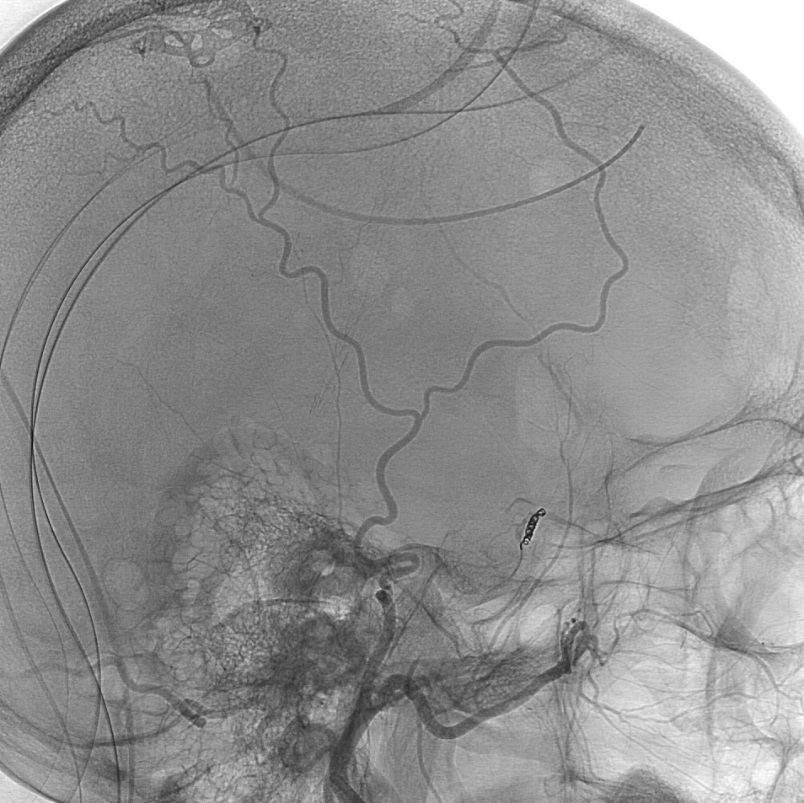

Post embolization angiogram: coil in middle meningeal artery